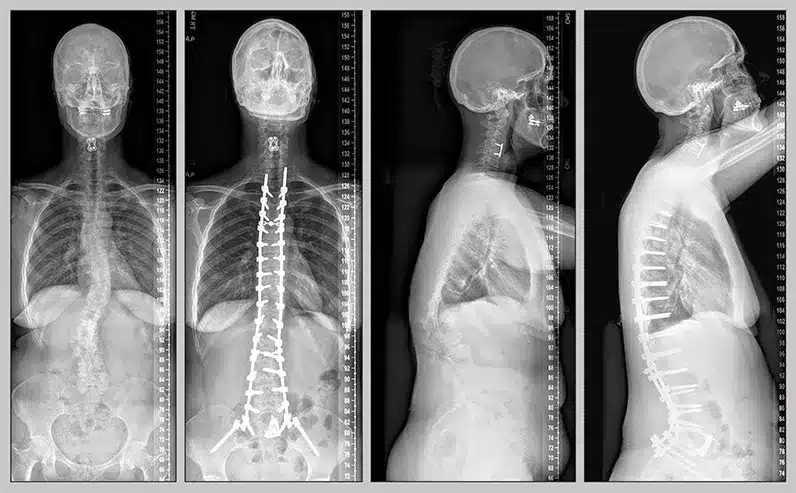

الجنف هو اضطراب عضلي عصبي يحدث في العمود الفقري والذي يؤدى إلى انحناء أو اعوجاج يغير من الشكل الظاهري للعمود الفقري، ويمكن أن يحدث مضاعفات أخرى منها تضرر الحبل الشوكي أو حدوث ضعف في الأعصاب والعضلات في الظهر ويصاحب هذا ألم شديد في الفقرات الموجودة في العمود الفقري واختلاف ما بين طول الكتفين.

- إذا كانت درجة انحناء العمود الفقري كبيرة فحينها يلجأ الطبيب إلى إجراء عملية الجنف من أجل إيقاف تطور انحناء العمود الفقري ومن ثم إعادته إلى شكله ووضعه الطبيعي.

- لا شك أن عملية الجنف تساعد بشكل كبير على أن يتخلص الشخص من البروز الواضح في ظهره، هذا بالإضافة إلى أن نسبة نجاح العملية تكون أعلى كلما كان العمود الفقري مرن أكثر وهذا يساعد على الحصول على عمود فقري قريب من الشكل الطبيعي له.

- تساعد عملية الجنف على الحفاظ على حركة الجسم بطريقة طبيعية حيث يهتم الطبيب بجعل عدد كبير من الفقرات غير مثبتة بالمعادن بحيث تكون حرة، وذلك من أجل الحفاظ على مرونة العمود الفقري أثناء أداء نشاطه اليومي المعتاد وممارسة الرياضة.

- عملية تثبيت ودمج الفقرات: يقوم الجراح بعمل تثبيت للفقرات التي حدث فيها انحناء في العمود الفقري ودمجها معا لكي يبدأ المصاب في الشعور تحسن ولكن يكون من الصعب عليه ثني الظهر مرة ثانية.

- بعد أن يرى الجراح العمود الفقري يقوم بوضع المسمامير أو الغرسات المعدنية التي تعمل على تثبيت الفقرات التي يرغب في تعديلها، ويتم ربط تلك المسامير مع بعضها البعض عن طريق استخدام قضبان مصنوعة من مادة التيتانيوم ومن ثم شد القضبان بطريقة محكمة إلى أن يعود العمود الفقري إلى الوضع الطبيعي له.